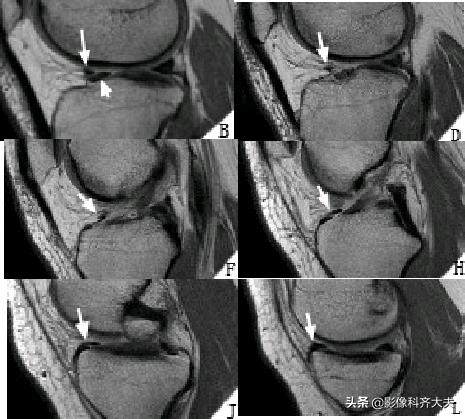

半月板损伤的MRI分级(0-III级)和形态学特征

О级:为正常半月板,表现为均匀低信号且形态规则

正常外侧半月板形态、信号均匀(0级)

Ⅰ级:不与半月板关节面相接触的灶性的椭圆或球形高信号。病理:半月板粘液样变性、软骨细胞缺乏或出现少细胞区

Ⅰ级变性:球状

Ⅱ级:表现为水平的、线形的半月板内高信号,可延伸至半月板的关节囊缘,但未达到半月板的关节面缘。病理:粘液变性范围较Ⅰ级大,显微镜下软骨基质的的多细胞区内可见裂隙和胶原碎片

Ⅲ级:半月板内高信号达一个或两个关节面。Ⅲ级A型:线形高信号达关节面。Ⅲ级B型:不规则高信号达关节面。表示一个确定撕裂。可为部分性或全层撕裂。常伴有症状。病理上可见纤维软骨断裂伴或不伴肉眼可见的表面蔓延 。